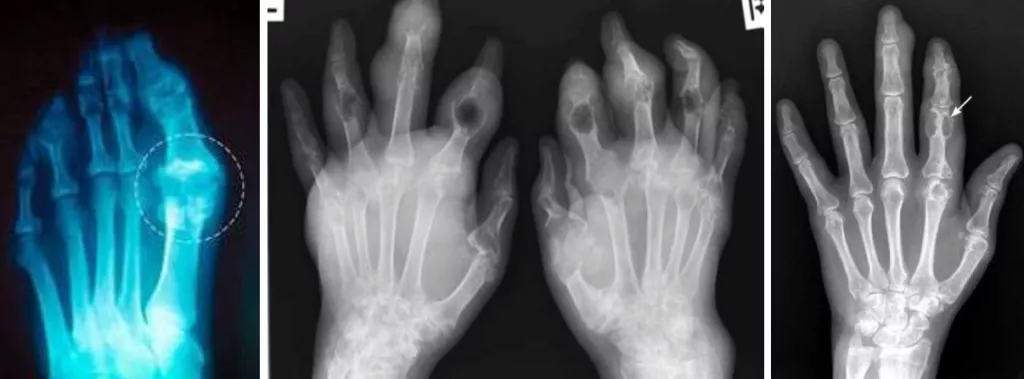

Рис 12. Тофусы кистей на рентгенограмме [8].

Рис 13, 14, 15. Симптом «пробойника» на рентгенограммах кистей пациентов с подагрой. Это рентгенологический признак, типичный для поздней подагры, представляет собой краевые костные эрозии или кистовидные образования правильной формы с четкими, иногда склерозированными контурами [8].